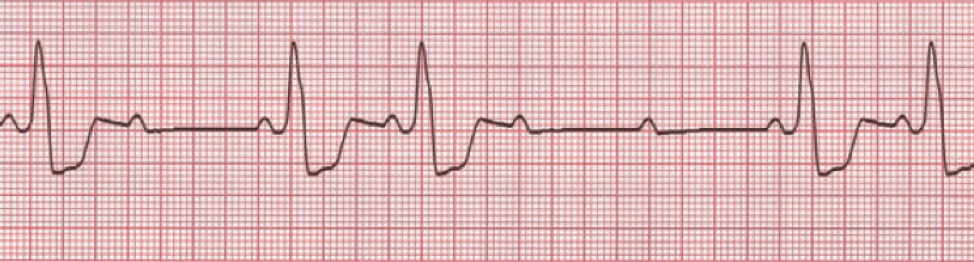

Since sinus bradycardia is a sinus rhythm with a pace below 60 beats per minute, the rhythm will have normal P waves originating from the sinoatrial node (upright in leads aVF, I, II, and III).

The P waves in sinus rhythm reflect the electrical activity in the atrium rather than AV node conduction or the response of the ventricle. Those should be evaluated by assessing the PR interval and the QRS morphology.

Sinus bradycardia can have other etiologies. For example, patients on beta-blockers, vagal stimulation, and high exercise tolerance from physical conditioning can all cause this rhythm, and treatment is not necessarily indicated. Inferior MI can be a pathologic cause.